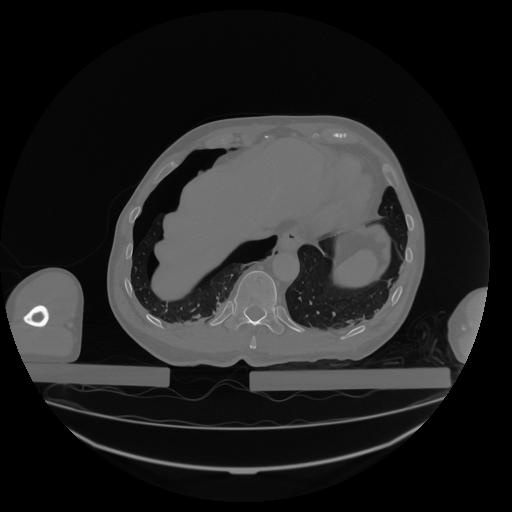

34 CUERPO,CE,Vol,1.0,CUERPO,,